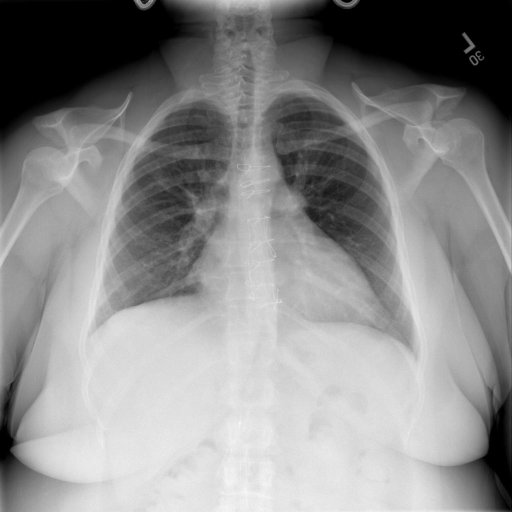

# 本文贡献 ![](./assets/images/xrayglm.png) - 借助ChatGPT以及公开的数据集,我们构造了一个`X光影像-诊断报告`对的医学多模态数据集; # 数据集 - [MIMIC-CXR](https://physionet.org/content/mimic-cxr-jpg/2.0.0/)是一个公开可用的胸部X光片数据集,包括377,110张图像和227,827个相关报告。 - [OpenI](https://openi.nlm.nih.gov/faq#collection)是一个来自印第安纳大学医院的胸部X光片数据集,包括6,459张图像和3,955个报告。 在上述工作中,报告信息都为非结构化的,不利于科学研究。为了生成合理的医学报告,我们对两个数据集进行了预处理,并最终得到了可以用于训练的**英文报告**。除此之外,为了更好的支持中文社区发展,借助ChatGPT的能力,我们将英文报告进行了中文翻译,并最终形成了可用于训练的数据集。 |数据集|数量|下载链接| |:-|:-|:-| |MIMIC-CXR-zh|-|-| |OpenI-zh|6,423|[诊疗报告](./data/Xray/openi-zh.json) 、[X光影像](https://pan.baidu.com/s/13GBsDMKf6xBZBSHpoWH_EA?pwd=k9sh)| # 快速上手 1. 安装环境 ```bash # 安装依赖 pip install -r requirements.txt # 国内换源安装依赖 pip install -i https://mirrors.aliyun.com/pypi/simple/ -r requirements.txt ``` 此时默认会安装`deepspeed`库(支持`sat`库训练),此库对于模型推理并非必要,同时部分`Windows`环境安装此库时会遇到问题。 如果想绕过`deepspeed`安装,我们可以将命令改为: ```bash # 安装依赖 pip install -i https://mirrors.aliyun.com/pypi/simple/ -r requirements_wo_ds.txt # 安装SwissArmyTransformer pip install -i https://mirrors.aliyun.com/pypi/simple/ --no-deps "SwissArmyTransformer>=0.3.6" ``` 2. 模型推理 # 效果展示 |X光影像|诊疗报告(医生)|XrayGLM| |:-|:-|:-| |![](./data/Xray/2_1.png)|根据X射线图像,心脏大小正常,肺部看起来很清晰。已经排除了肺炎、积液、水肿、气胸、腺病、结节或肿块的存在。该发现表明一切正常。换句话说,总体印象是胸部正常。|X光片显示,心脏大小正常。肺部没有气胸或胸腔积液的证据。骨骼结构看起来没有任何异常。总的来说,X光片表明没有发现急性心肺疾病的迹象。| # 项目致谢 1. [VisualGLM-6B](https://github.com/THUDM/VisualGLM-6B)为我们提供了基础的代码参考和实现; 2. [MiniGPT-4](https://github.com/Vision-CAIR/MiniGPT-4)为我们这个项目提供了研发思路; 3. ChatGPT生成了高质量的中文版X光检查报告以支持XrayGLM训练; 4. [gpt_academic](https://github.com/binary-husky/gpt_academic)为文档翻译提供了多线程加速; 5. [MedCLIP](https://github.com/RyanWangZf/MedCLIP) 、[BLIP2](https://huggingface.co/docs/transformers/main/model_doc/blip-2) 、[XrayGPT](https://github.com/mbzuai-oryx/XrayGPT) 等工作也有重大的参考意义; ![](./assets/images/mpu.png) 这项工作由[澳门理工大学应用科学学院](https://www.mpu.edu.mo/esca/zh/index.php)硕士生[王荣胜](https://github.com/WangRongsheng) 、[段耀菲](https://github.com/IsBaSO4) 、[李俊蓉](https://github.com/lijunrong0815)完成,同时这项工作受到[檀韬](https://scholar.google.com/citations?hl=zh-CN&user=lLg3WRkAAAAJ)副教授、[彭祥佑](http://www.patrickpang.net/)老师的帮助支持。 *特别鸣谢:[USTC-PhD Yongle Luo](https://github.com/kaixindelele) 提供了有3000美金的OpenAI账号,帮助我们完成大量的X光报告翻译工作 # 免责声明 本项目相关资源仅供学术研究之用,严禁用于商业用途。使用涉及第三方代码的部分时,请严格遵循相应的开源协议。模型生成的内容受模型计算、随机性和量化精度损失等因素影响,本项目无法对其准确性作出保证。即使本项目模型输出符合医学事实,也不能被用作实际医学诊断的依据。对于模型输出的任何内容,本项目不承担任何法律责任,亦不对因使用相关资源和输出结果而可能产生的任何损失承担责任。 # 项目引用 如果你使用了本项目的模型,数据或者代码,请声明引用: ```bash @misc{wang2023XrayGLM, title={XrayGLM: The first Chinese Medical Multimodal Model that Chest Radiographs Summarization}, author={Rongsheng Wang, Yaofei Duan, Junrong Li, Patrick Pang and Tao Tan}, year={2023}, publisher = {GitHub}, journal = {GitHub repository}, howpublished = {\url{https://github.com/WangRongsheng/XrayGLM}}, } ``` # 使用许可 此存储库遵循[CC BY-NC-SA](https://creativecommons.org/licenses/by-nc-sa/4.0/) ,请参阅许可条款。